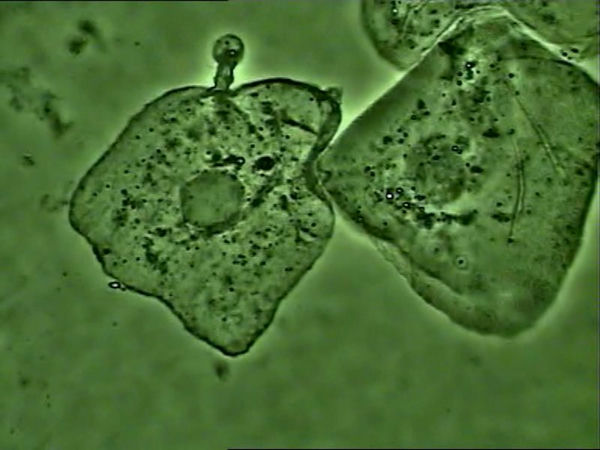

·显微镜下的肺炎支原体

支原体感染的细胞

支原体主要黏附在细胞膜上生存,使用光学显微镜高倍相衬观察,如果看到细胞核周围大量静止或布朗运动的小黑点,可以推断大概率为支原体。